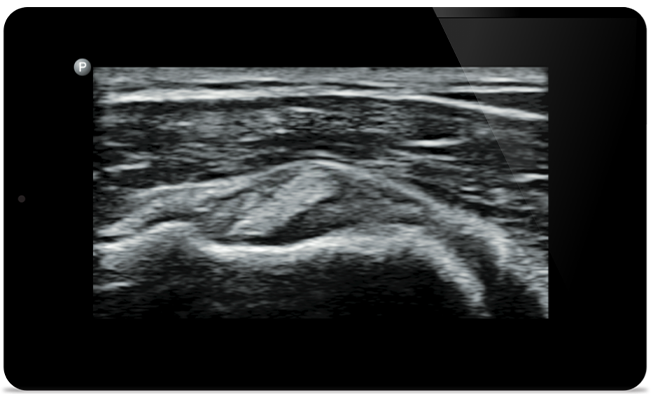

Punkcja stawu kolanowego

pod kontrolą ultrasonografii

Rozdarcie ścięgna mięśnia nadgrzebieniowego